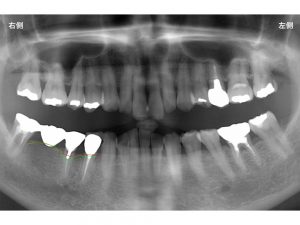

下顎右側奥歯が虫歯と歯根破折で抜歯となったケースです。

まず骨の状態です。

現在骨の位置は以下の赤線にあります。

抜歯予定の歯は、その奥の欠損と比べると

骨が少し吸収しています。

抜歯をすると歯を支えていた骨は多少なり吸収を起こします。

以下の緑線の位置ぐらいまでです。